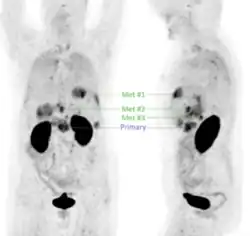

68Ga-Trivehexin PET image of a female patient with pancreatic ductal adenocarcinoma (PDAC), shown as maximum intensity projections in frontal (left) and lateral (right) position. The primary tumor in the pancreatic head (labeled 'Primary') and a total of 7 liver metastases (the 3 largest are labeled Met#1, Met#2 and Met#3) are clearly delineated. Due to renal excretion, a prominent signal is observed in the kidneys (center of images) and in the contents of the urinary bladder (lower image regions).[1]

First-in-human application of different αvβ6-integrin radiotracers has demonstrated that 68Ga-Trivehexin performed especially well in detecting pancreatic cancer, showing high uptake in tumor lesions and low background in the gastrointestinal tract (GI tract) (see image).[30] Since its introduction,[1] 68Ga-Trivehexin has been used predominantly for PET/CT imaging of pancreatic ductal adenocarcinoma (PDAC), for example, in single cases [28][31] and two cohorts (12 and 44 patients, respectively) [32][29] of suspected or known PDAC.